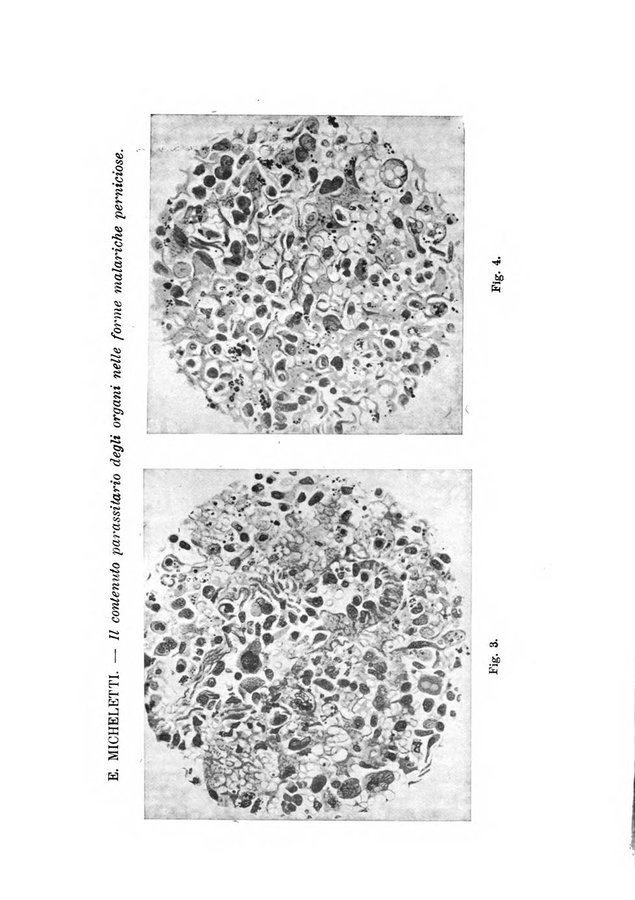

Annali di medicina navale e coloniale

V.2

1930